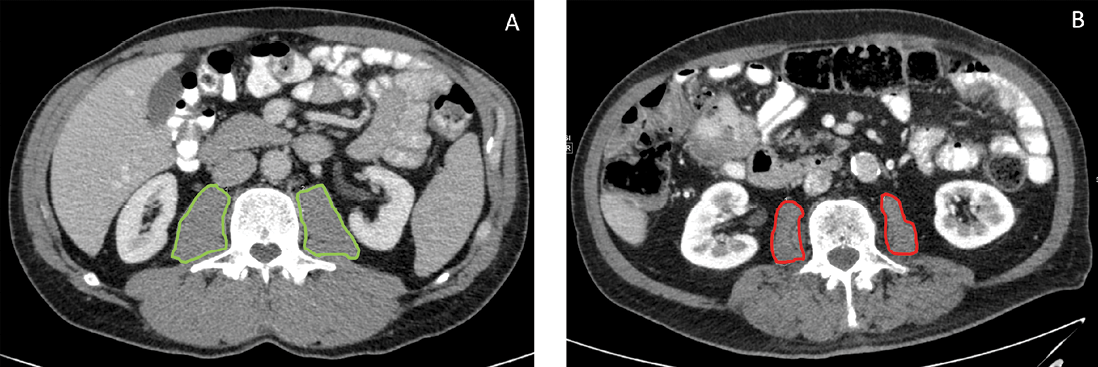

In der onkologischen Viszeralchirurgie hat sich zur Bestimmung der Sarkopenie der Total Psoas Index (TPI) etabliert [16]. Der TPI setzt die beidseitige Fläche des M. psoas auf Höhe von LWK 3 ins Verhältnis zur Körpergröße (Info-Box 3).

Da vor einer größeren Operation in der Regel eine Computertomographie des Abdomens zur Diagnostik erfolgt, lässt sich in dieser Untersuchung das Vorliegen einer Sarkopenie in wenigen Minuten über den TPI detektieren (Abb. 4). Der TPI kann auch in extern durchgeführten CTs ermittelt werden.

Info 3: Total Psoas Index (TPI) als ein Maß für Sarkopenie [16].

TPA: total psoas area: beidseitige Fläche des M. psoas auf Höhe LWK 3 in mm2.

Normalwerte: Frauen: > 385 mm2/m2, Männer: > 545mm2/m2.

Abb. 1: TPI-Messung im CT. A: Patient ohne Sarkopenie mit normalem TPI. B: Sarkopener Patient mit erniedrigtem TPI